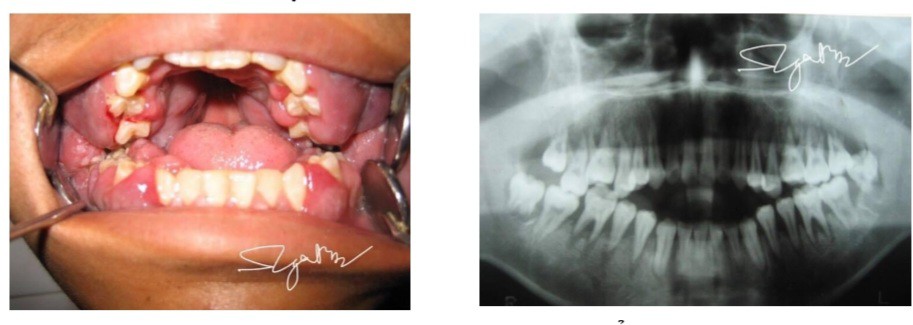

Hình ảnh bé trai 16 tuổi bị viêm lợi.

Khám bệnh nhân tỉnh, mệt mỏi, da xanh niêm mạc nhợt, sốt 38,5 độ C. Tại chỗ có hình thái thương tổn vô cùng đặc biệt: miệng ngậm không kín, hở cửa, chỉ có 2 răng hàm chạm nhau, lợi 2 hàm thâm nhiễm cực nặng, răng toàn bộ 2 hàm lung lay độ 2, 3. X.quang panorama cũng cho thấy hình ảnh đặc biệt: toàn bộ nhóm răng hàm trên + dưới 2 bên bị đẩy chồi khỏi huyệt ổ răng (đây cũng là lí do hiện tại bệnh nhân bị hở cửa, chỉ có 2 răng hàm trong cùng chạm nhau).

Ngay lập tức, bệnh nhân được xét nghiệm công thức máu cấp, kết quả bạch cầu là 140.000 G/l. Sau khi mời hội chẩn huyết học, bằng các xét nghiệm chuyên sâu, bệnh nhân được chẩn đoán leucemie cấp và được chuyển điều trị theo đúng chuyên khoa.